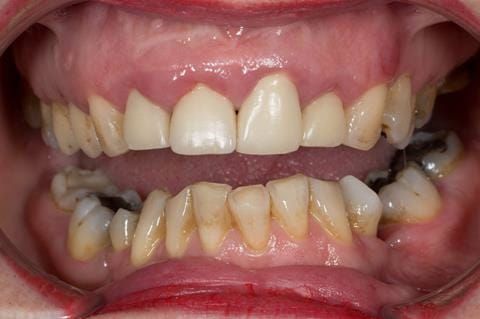

- High smile line showing gum above gingival zeniths of upper front teeth when smiling. Aesthetic failure of the upper four incisors with inflammation of the gingivae and mis-match of the gingival zenith levels.

- Other than the maxillary incisors the remaining dentition was in marginally better condition being moderately to heavily restored. Many will probably require replacement and restoration from time to time mainly from wear and tear owing to occlusal forces.

- UR2 peri-radicular periodontitis with a peri-radicular area on the root apex. Retrograde amalgam filling from a previous apicectomy. No visible root canal or root canal filling. Large circumferential marginal gap between the crown and tooth. Large post and core present. Very little tooth structure remaining resulting in a fragile tooth with increased potential for fracture.

- UR1 peri-radicular periodontitis with a small peri-radicular area on the root apex with wide blunderbuss apex. Radio-opaque root canal filling present approximately 3 mm short of the radiographic apex. Large circumferential marginal gap between the crown and tooth. Large post and core present. Very little tooth structure remaining resulting in a fragile tooth with increased potential for fracture.

- UL1 peri-radicular periodontitis with a peri-radicular area on the root apex. Retrograde amalgam filling from a previous apicectomy. Visible root canal space with no sign of root canal filling. Large circumferential marginal gap between the crown and tooth. Large post and core present. Very little tooth structure remaining resulting in a fragile tooth with increased potential for fracture.

- UL2 peri-radicular periodontitis with a peri-radicular area on the root apex. No visible root canal or root canal filling. Large circumferential marginal gap between the crown and tooth. Large post and core present. Very little tooth structure remaining resulting in a fragile tooth with increased potential for fracture.

Following consultation and second discussion appointment the patient chose to have option 3 namely, a maxillary cobalt chromium based partial denture/protective occlusal splint. The clinical situation and treatment process is shown in detail below with photographs. The patient was successfully rehabilitated with this and her quality of life considerably improved. The clinical work was provided by Finlay and the technical work by Rowan.